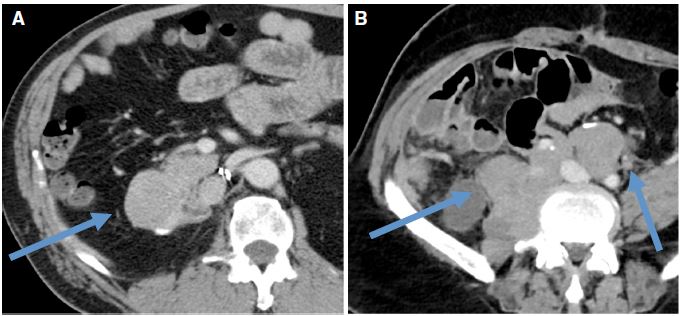

Introduction. Retroperitoneal soft tissue sarcomas (RPS) are rare tumors. Surgery is the mainstay of curative therapy, but local recurrence is common. No recommendations concerning the best management of recurring disease have been developed so far. Although every effort should be made to optimize the initial approach, recommendations to treat recurring RPS will be helpful to maximize disease control at recurrence.

Results. Recurrent RPS management was evaluated from diagnosis to follow-up. It is a rare and complex malignancy that is best managed by an experienced multidisciplinary

team in a specialized referral center. The best chance of cure is at the time of primary presentation, but some patients may experience prolonged disease control also at recurrence, when the approach is optimized and follows the recommendations contained herein.